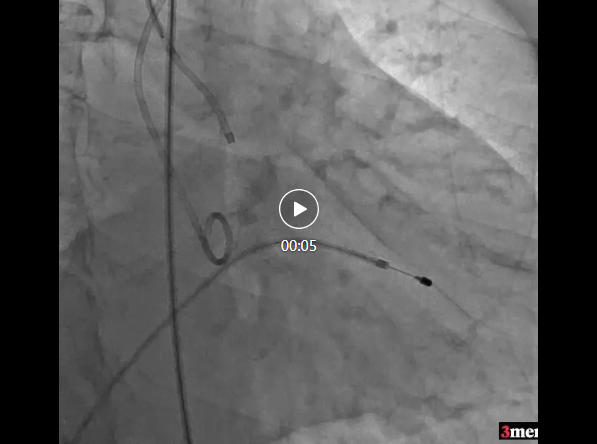

跨瓣